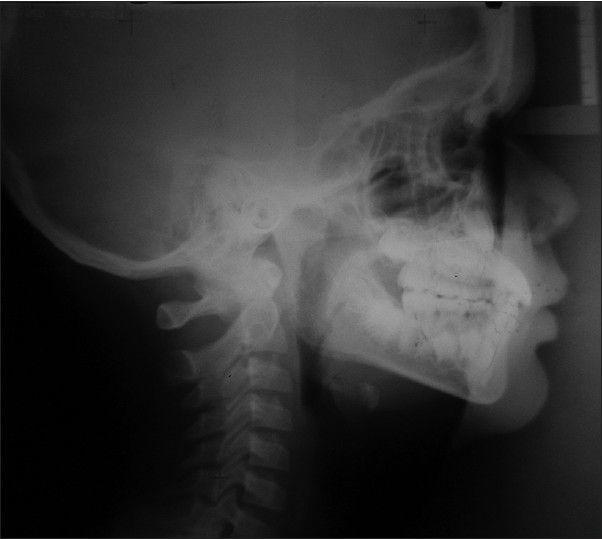

Most developing Class III patients display a retruded maxilla. Early intervention in mixed dentition is associated with better patient compliance and possibly a better orthopedic response, which can produce favorable results. The aim of this article is to present the fabrication of the new modified tandem appliance and its use in management of developing Class III malocclusion. The therapeutic results of a new modified tandem appliance are presented in an 8 year-old male patient with anterior cross bite and retrognathic maxilla at the mixed dentition stage. Anterior cross bite was corrected in 3 months and the positive overjet of 4 mm after continued use of the appliance for 1 year. There was a significant improvement in profile of the patient. The use of this appliance in this type of malocclusion enabled the correction of malocclusion in a few months and encouraging favorable skeletal growth in the future.

大多数处于生长发育期的III类患者表现出上颌后缩。在混合牙列期进行早期干预,患者的依从性更好,并且可能获得更好的矫形反应,从而产生良好的效果。本文的目的是介绍新型改良串联矫治器的制作及其在生长发育期III类错牙合畸形治疗中的应用。本文展示了一名8岁男性患者在混合牙列期使用新型改良串联矫治器治疗前牙反牙合和上颌后缩的治疗结果。3个月内前牙反牙合得到矫正,继续使用矫治器1年后覆盖达到4mm的正值。患者的侧貌有显著改善。在这类错牙合畸形中使用该矫治器,能够在几个月内矫正错牙合,并有望在未来促进有利的骨骼生长。